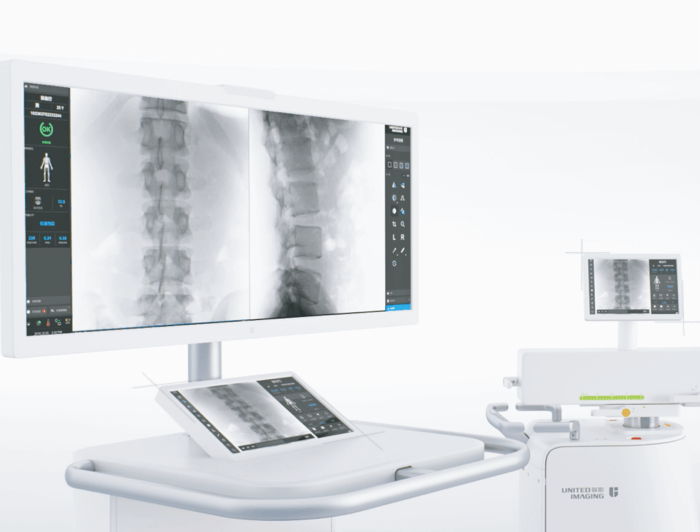

智能参数匹配

不同临床场景智能适配曝光参数,随心选择动态与静态图像工作模式,临床影像高清呈现。